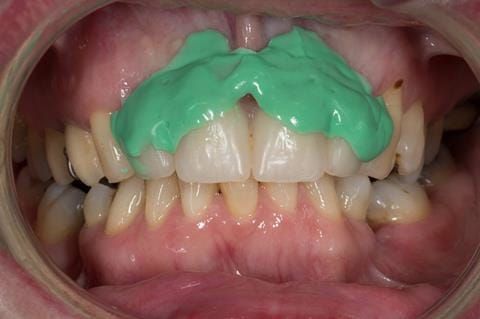

Provision of a maxillary cobalt chromium based partial denture/protective occlusal splint in a heavily restored dentition

- Extract the upper 2-2 teeth and replace with an interim acrylic based partial denture. Reline the interim denture over 9 - 12 months, replacing with a definitive cobalt chromium based partial denture. The definitive denture would ideally be designed as an occlusal protective splint to reduce the the potential for mechanical wear and breakages of the moderately/heavily restored maxillary dentition. In addition, should further upper teeth require extraction they could be added on to the denture cobalt chromium framework - therefore a new prosthesis would not be required as future teeth are lost. This option would produce an excellent aesthetic outcome. This is the option the patient chose to have.

Following consultation and second discussion appointment the patient chose to have option 3 namely, a maxillary cobalt chromium based partial denture/protective occlusal splint. The clinical situation and treatment process is shown in detail below with photographs. The patient was successfully rehabilitated with this and her quality of life considerably improved. The clinical work was provided by Finlay and the technical work by Rowan.